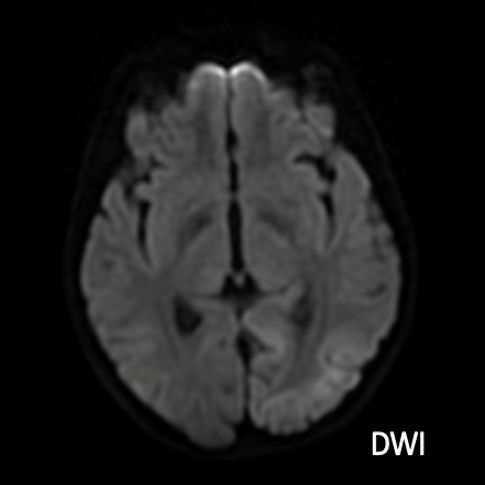

- A) Aksiyel FLAIR görüntülerde parietooksipital lobda kortikal hiperintensite (ok) ve difüzyon görüntülerde kısıtlanma alanları izleniyor (oklar). Ertesi gün çekilen kontrol MRG’de FLAIR serilerde yeni gelişen oksipital bölgede kortikal hiperintensite (ok) izlenmektedir.

- MELAS sendromunun radyolojik özellikleri, klasik iskemik inmeden farklı olarak vasküler sulama alanlarına uymayan ve migratuar stroke-benzeri lezyonlar ile karakterizedir.

- MRG’de akut fazda T2/FLAIR hiperintensiteyle birlikte giral şişme ile karakterize enfarkt-benzeri lezyonlar ve subkortikal beyaz cevher tutulumu görülür. DWI’da artmış sinyal dikkat çekmekle birlikte ADC değerlerinin normal ya da hafif artmış olması, baskın sürecin vazojenik ödem olduğunu gösterir.